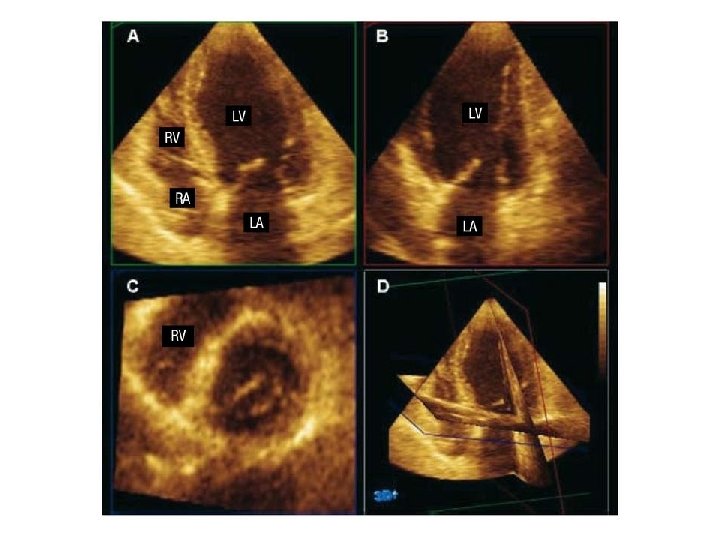

APICAL 4 CHAMBER VIEW